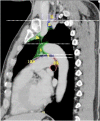

The purpose of this study was to develop a consensus-based computed tomographic (CT) atlas that defines lymph node stations in radiotherapy for lung cancer based on the lymph node map of the International Association for the Study of Lung Cancer (IASLC). A project group in the Japanese Radiation Oncology Study Group (JROSG) initially prepared a draft of the atlas in which lymph node Stations 1-11 were illustrated on axial CT images. Subsequently, a joint committee of the Japan Lung Cancer Society (JLCS) and the Japanese Society for Radiation Oncology (JASTRO) was formulated to revise this draft. The committee consisted of four radiation oncologists, four thoracic surgeons and three thoracic radiologists. The draft prepared by the JROSG project group was intensively reviewed and discussed at four meetings of the committee over several months. Finally, we proposed definitions for the regional lymph node stations and the consensus-based CT atlas. This atlas was approved by the Board of Directors of JLCS and JASTRO. This resulted in the first official CT atlas for defining regional lymph node stations in radiotherapy for lung cancer authorized by the JLCS and JASTRO. In conclusion, the JLCS-JASTRO consensus-based CT atlas, which conforms to the IASLC lymph node map, was established.